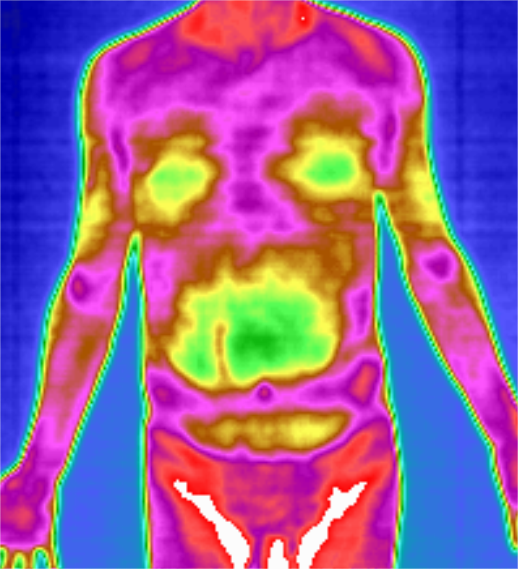

热成像扫描技术是近年来成功应用于临床的一项新的临床影像辅助诊断技术。医···

任何高于绝对零度-273.15℃的物体,由于原子和分子结构内部的无规则···

全维度热成像扫描系统(GTT)是新一代高精度多功能医用热成像扫描分析系···